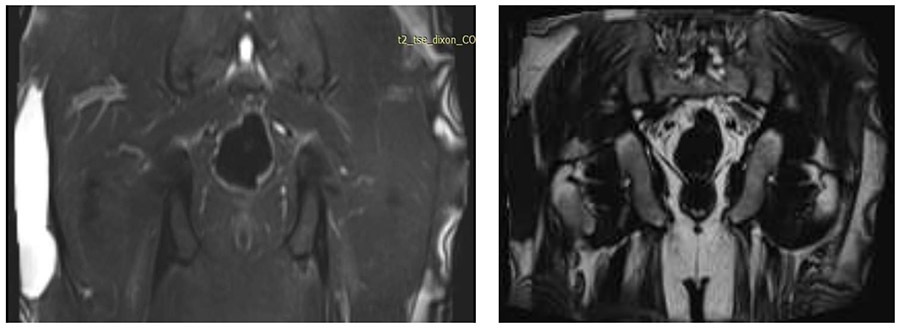

Ameliyat Öncesi: MR’da uyluk lateralde düzensiz sınırlı kalıntı kitle görülmekte